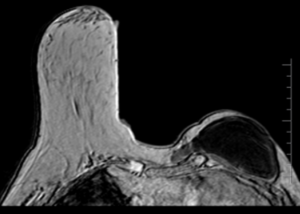

52 year old lady with right breast mass of recent onset.

What is the mass?

Clue: She is IDDM since 15 years